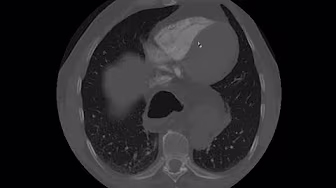

Today, I review, link to, and embed How to read a CTPA and diagnose a PE (CT pulmonary angiogram – pulmonary embolism) from Turkleton Radiology.

Jul 27, 2022CTPA is performed to evaluate for pulmonary embolism. This video is my approach in reading a CTPA.